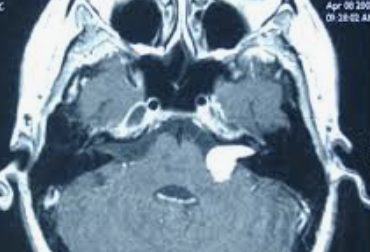

Tumeur nerveuse bénigne développée aux dépens du nerf acoustique, encore appelée schwannome, car elle naît précisément des cellules de la gaine du nerf, les cellules de Schwann.

Le neurinome est bénin, mais la chirurgie proposée n’est pas anodine.

On peut utiliser une radiothérapie exclusive (le gamma knife) qui délivre en une fois une radiothérapie gamma, quand c’est une bonne indication, sur le site tumoral.